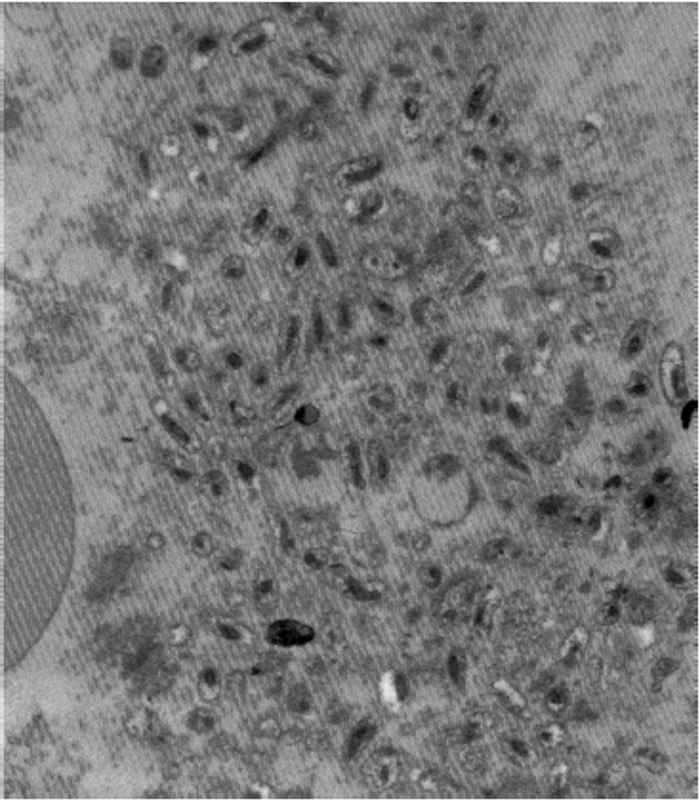

During infections, C. burnetii bind to receptors on monocytes/macrophages and are internalized in phagosomes which rapidly fuse with lysosomes to form phagolysosomes that appear as large vacuoles in infected cells.21 Coxiella burnetii is an acidophilic bacterium and its metabolism is enhanced by the acidic pH in the phagolysosome. 97 There are two distinct morphological forms of C. burnetii.53 The ‘small cell variant’ (SCV) is a compact, small rod with a very electron-dense centre of condensed nucleoid filaments while the ‘large cell variant’ (LCV) is a large, less dense, pleomorphic organism with a clear, periplasmic space between the outer and cytoplasmic membranes (Figure 43.1). A dense endospore-like body 130 to 170 nm in diameter might be found at one pole of some LCV (Figure 43.2). Both forms multiply by transverse binary fission. The SCVs are metabolically inactive and are the extracellular form of the organism. Once taken into the phagolysosome they are activated by the acidic environment and form LCVs, the metabolically active intracellular form of the bacterium. The cytoplasm of the host cell becomes filled with vacuoles loaded with organisms (Figure 43.3). ‘Large cell variants’ undergo sporogenic differentiation and form resistant, spore-like forms of the bacteria. These develop to SCVs that are released when the cells lyse.